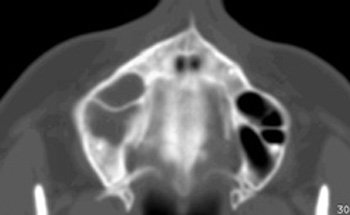

Con sospecha de sinusitis maxilar derecha crónica de probable origen odontógeno, se solicita una tomografía computarizada (TC) de senos paranasales, observándose una ocupación del seno maxilar y etmoides anterior derecho, en probable relación con quiste periapical de pieza 1.6 y posible disrupción focal del suelo del seno (ver Imágenes nº 1-3 al final del texto).

Imagen nº1: TC corte coronal.

Imágenes 2 y 3: TC cortes axiales.